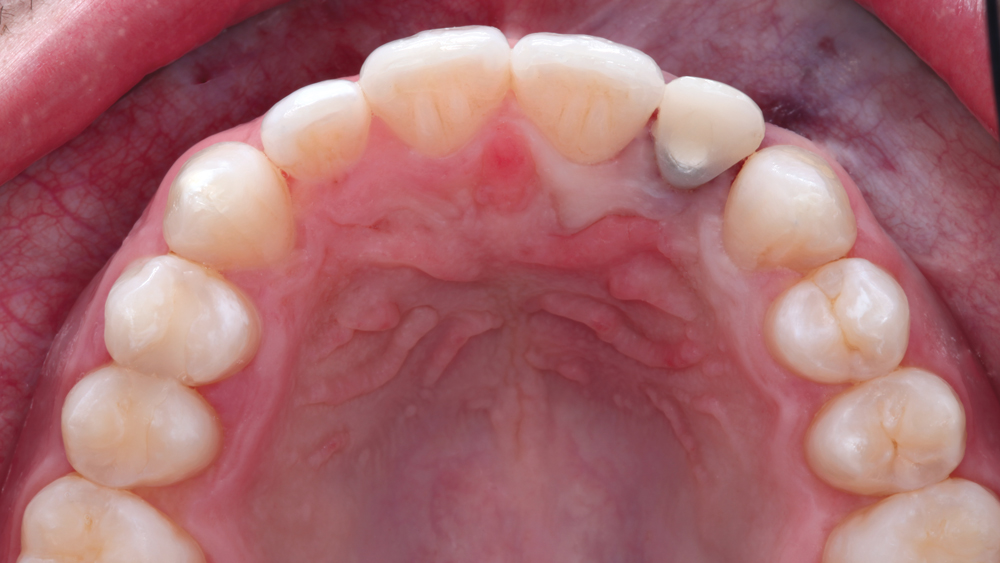

The following case illustrates the efficient, straightforward clinical workflow for placing Hahn Tapered Implants via guided surgery. A digital treatment plan is developed in which a 3.5 mm implant is positioned to support the ideal prosthetic outcome. An immediate provisional crown is designed in concert with the surgical guide and delivered at the time of surgery, helping to produce a predictable, highly esthetic restoration for a demanding case in the smile zone.